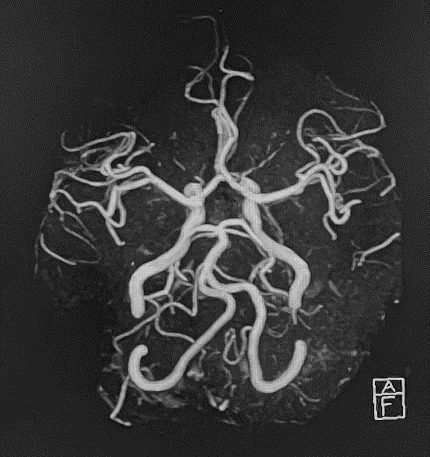

既に定評のある、脳神経、骨関節領域の他に、MRアンギオ(脳血管・四肢血管が描出可能)、MRCP(造影剤を用いない胆管・膵管画像)、急性期脳梗塞の診断(拡散強調像、MRアンギオや灌流画像を組み合わせることで治療方針の決定に有用)などの撮像法にも対応可能です。